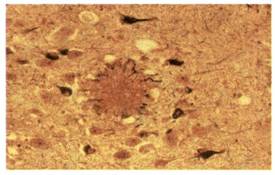

Η νόσος αυτή προσβάλλει στις ανεπτυγμένες χώρες το 5% των ατόμων ηλικίας πάνω από 65 ετών και το 20% των ατόμων ηλικίας πάνω από 80 ετών. Οδηγεί στην άνοια (προοδευτική απώλεια των πνευματικών λειτουργιών, ανεξάρτητη από αυτήν που συνοδεύει τη γήρανση του εγκεφάλου). Τα άτομα που προσβάλλονται από τη νόσο εμφανίζουν απώλεια μνήμης, μειωμένη ικανότητα σκέψης και λογικής αιτιολόγησης, δυσκολίες στην επικοινωνία με άλλα άτομα, ακόμα και ανικανότητα στην εκπλήρωση απλών καθημερινών

δραστηριοτήτων. Στους πάσχοντες παρατηρήθηκαν ανωμαλίες σε νευρώνες, κυρίως σε περιοχές του φλοιού των ημισφαιρίων. Στις περιοχές αυτές παρατηρούνται εξωκυτταρικές εναποθέσεις (αμυλοειδείς πλάκες), λόγω συσσώρευσης μίας μικρού μοριακού βάρους πρωτεΐνης, της β-αμυλοειδούς πρωτεΐνης. Η αυξημένη συγκέντρωση της πρωτεΐνης αυτής οδηγεί πιθανώς στη λύση των λυσοσωμάτων, με συνέπεια την καταστροφή των νευρικών κυττάρων. Η πρωτεΐνη αυτή αποτελεί τμήμα μιας άλλης πρόδρομης πρωτεΐνης, της ΑΡΡ (Amyloid Precusor Protein), που φυσιολογικά βρίσκεται στην κυτταρική μεμβράνη των νευρώνων και άλλων κυττάρων. Μία μορφή της νόσου φαίνεται να είναι κληρονομική. Έχει απομονωθεί γονίδιο στο 21ο ζεύγος των χρωμοσωμάτων, το οποίο καθορίζει τη δομή της πρόδρομης πρωτεΐνης. Η γονιδιακή αυτή θέση αποκτά ιδιαίτερο ενδιαφέρον, διότι όλα σχεδόν τα άτομα που πάσχουν από το σύνδρομο Down (τρισωμία 21) και επιβιώνουν μετά τα 35 έτη εμφανίζουν συμπτώματα της ασθένειας Alzheimer.

Αμυλοειδής πλάκα (στο κέντρο της φωτογραφίας) σε

εγκεφαλικό ιστό ατόμου που

πάσχει από νόσο Alzheimer